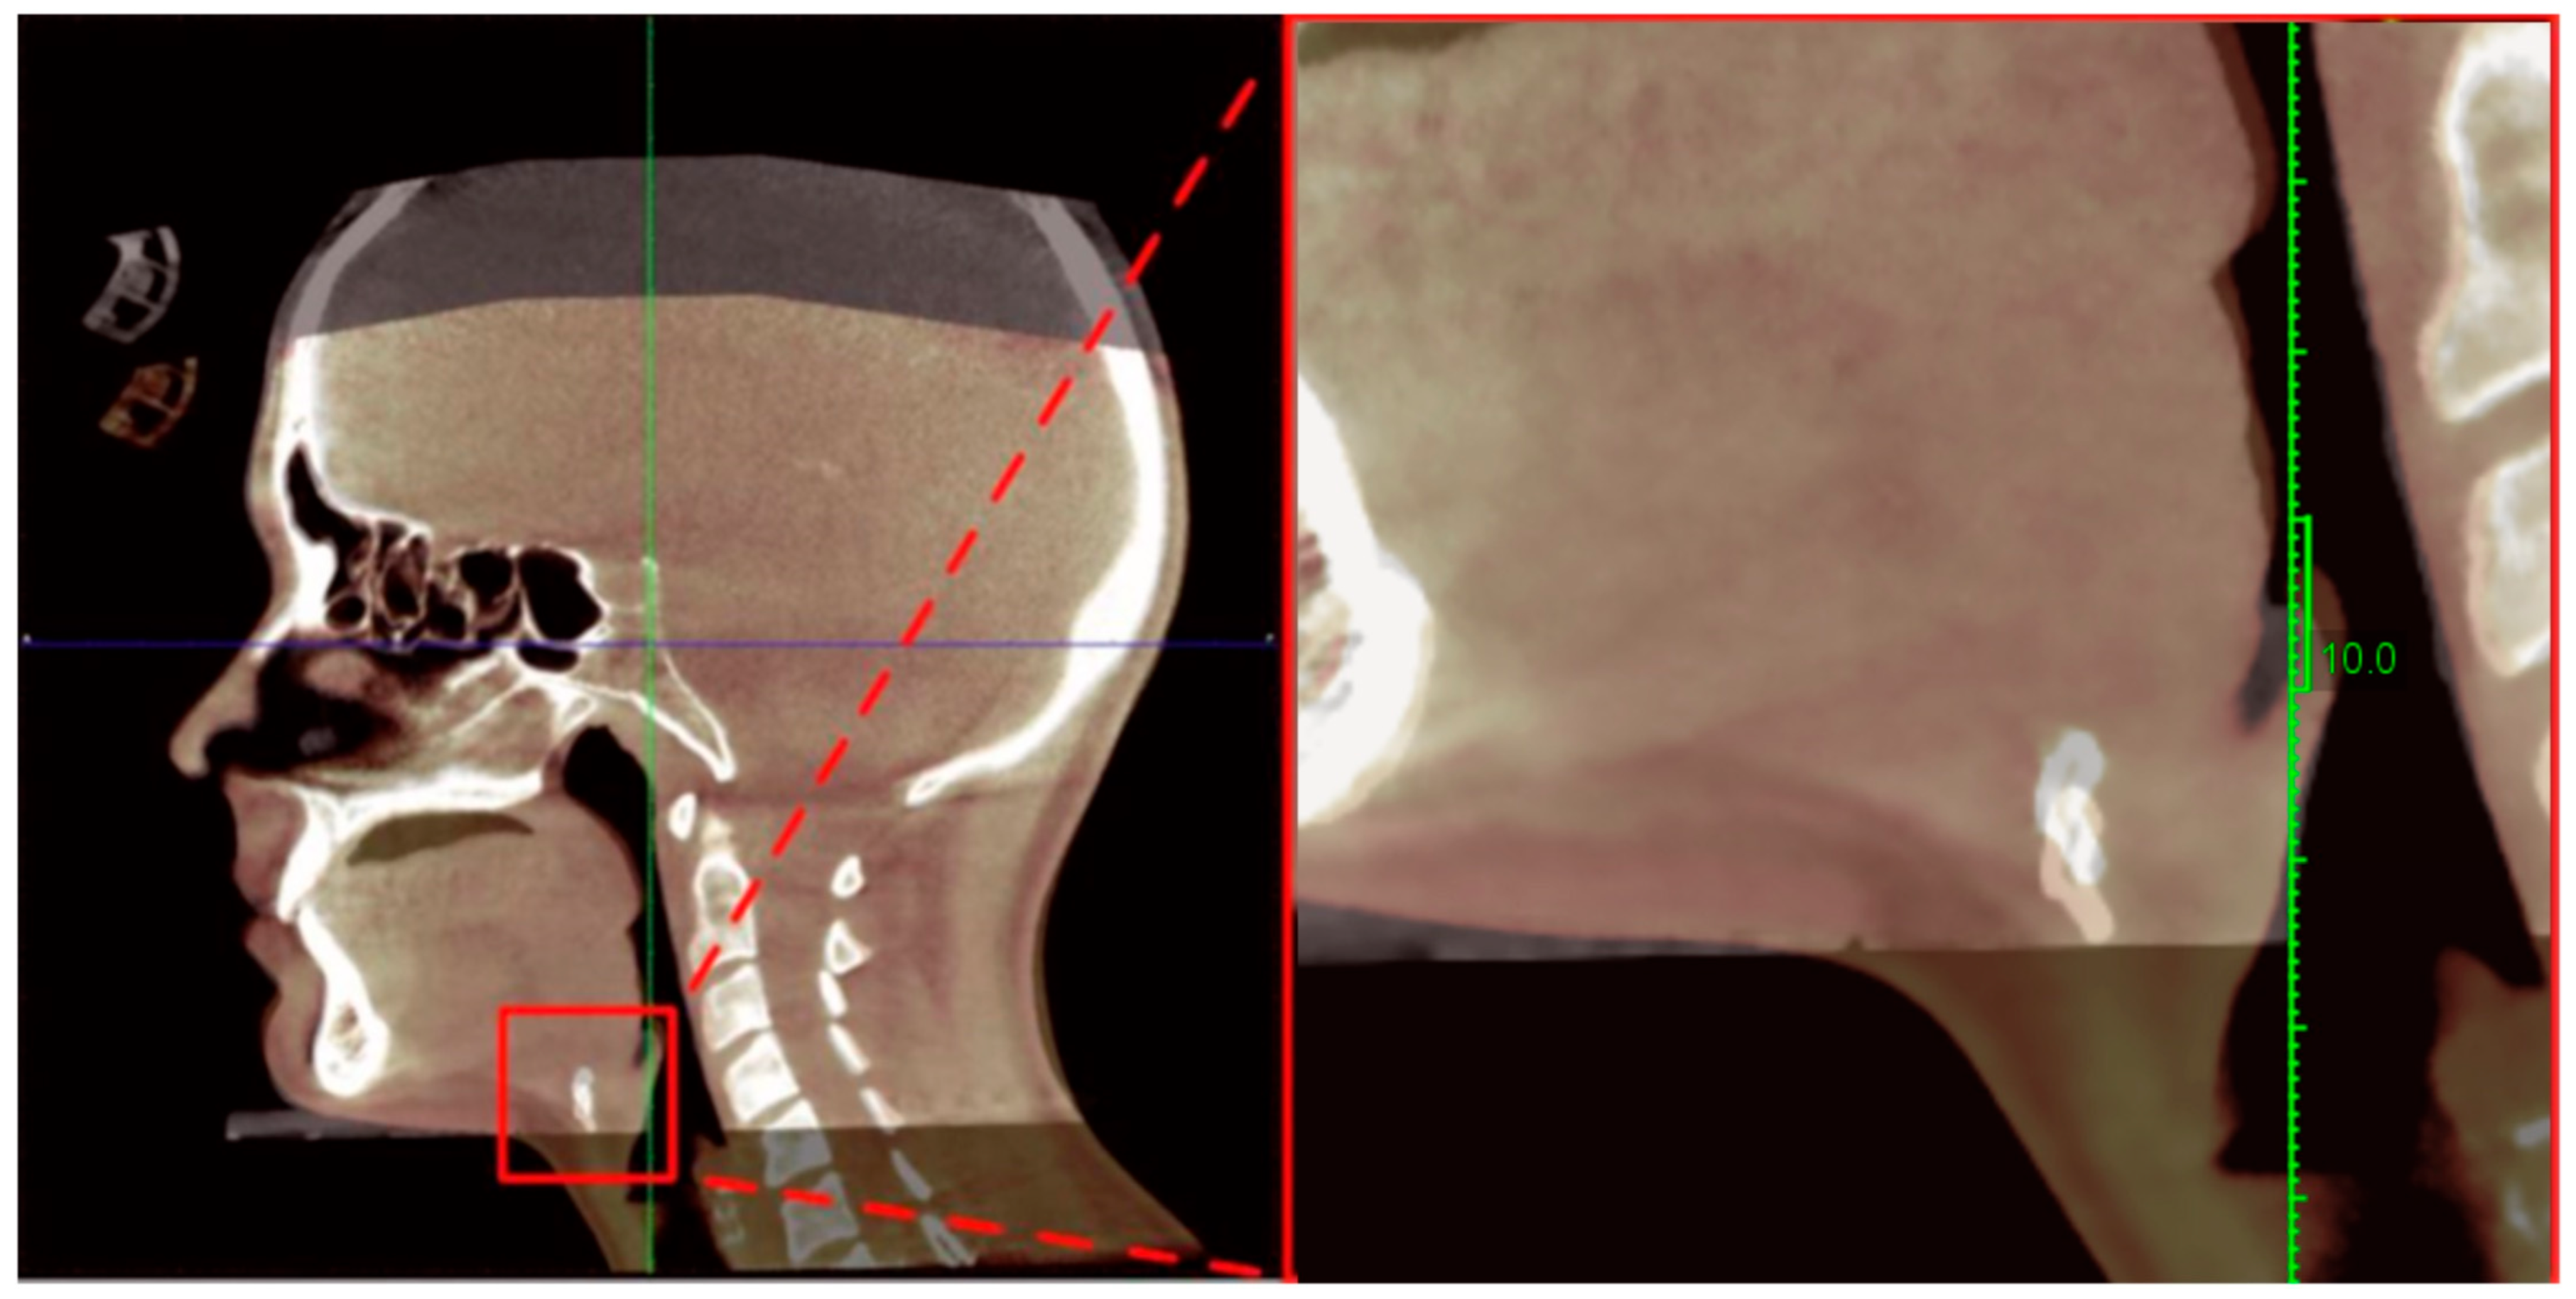

2.4.1. Cephalometric and Hyoid Imaging Outcomes (Primary Outcomes)

| H | Hyoidale | The most superior and anterior point on the body of the hyoid bone. |

| Phw | Posterior Pharyngeal Wall | The posterior wall of the pharynx at the oropharyngeal level. |

| aiC2, aiC3, aiC4 | Anterior–Inferior Points of Cervical Vertebrae C2–C4 | The most inferior–anterior points of the respective cervical vertebral bodies. |

| asC3 | Anterior–Superior Point of C3 | The most superior–anterior point on the C3 vertebral body. |